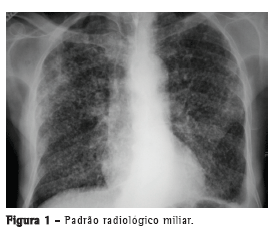

Com relação aos achados radiológicos, infiltrados reticulares e consolidação são os padrões mais frequentes,(5,6,10,15,17) sendo que cavitação pode estar presente em 27-50% dos casos.(6,10,16) As Figuras 1 a 4 mostram alguns dos principais padrões radiológicos nesse contexto.

O tempo entre o início dos sintomas e o início do tratamento antituberculose descrito nos estudos foi maior do que 30 dias em 28,8-34,0% dos casos.(6,17) O tempo entre a admissão e o início da terapêutica adequada foi avaliado em apenas um estudo, sendo relatada uma média de 4,3 dias. Naquele estudo retrospectivo, o tempo entre a admissão e o início do tratamento foi menor nos pacientes com tuberculose miliar do que naqueles com pneumonia tuberculosa (2,8 ± 2,5 dias vs. 5,0 ± 7,0 dias; p = 0,048).(16) Pode haver atraso no diagnóstico e, consequentemente, no começo do tratamento pela difícil diferenciação radiológica entre pneumonia tuberculosa e pneumonia bacteriana grave. Considerando essa dificuldade na distinção entre as duas patologias, um estudo avaliou as diferenças nas características clínicas e radiológicas de pacientes com pneumonia grave com e sem tuberculose internados em UTIs. A história de sintomas com duração maior do que duas semanas e a presença de micronódulos ou de padrão cavitário na radiografia de tórax foram significativamente associados com tuberculose pulmonar ativa.(20) Adicionalmente, o padrão miliar na radiografia de tórax também pode ser erroneamente interpretado como insuficiência cardíaca congestiva.(18)